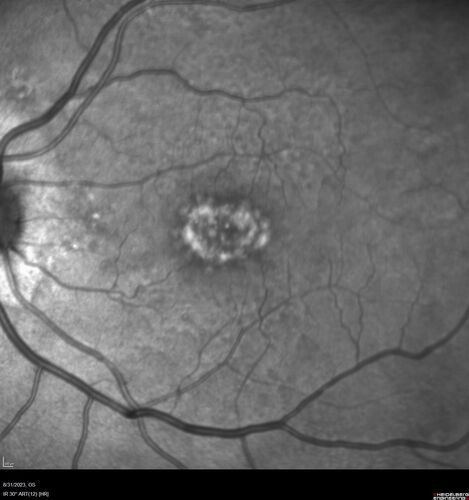

Dry Macular Degeneration with Pseudodrusen and vitelliform lesion

80 year old female with 20/50 vision in both eyes. Mild blurring